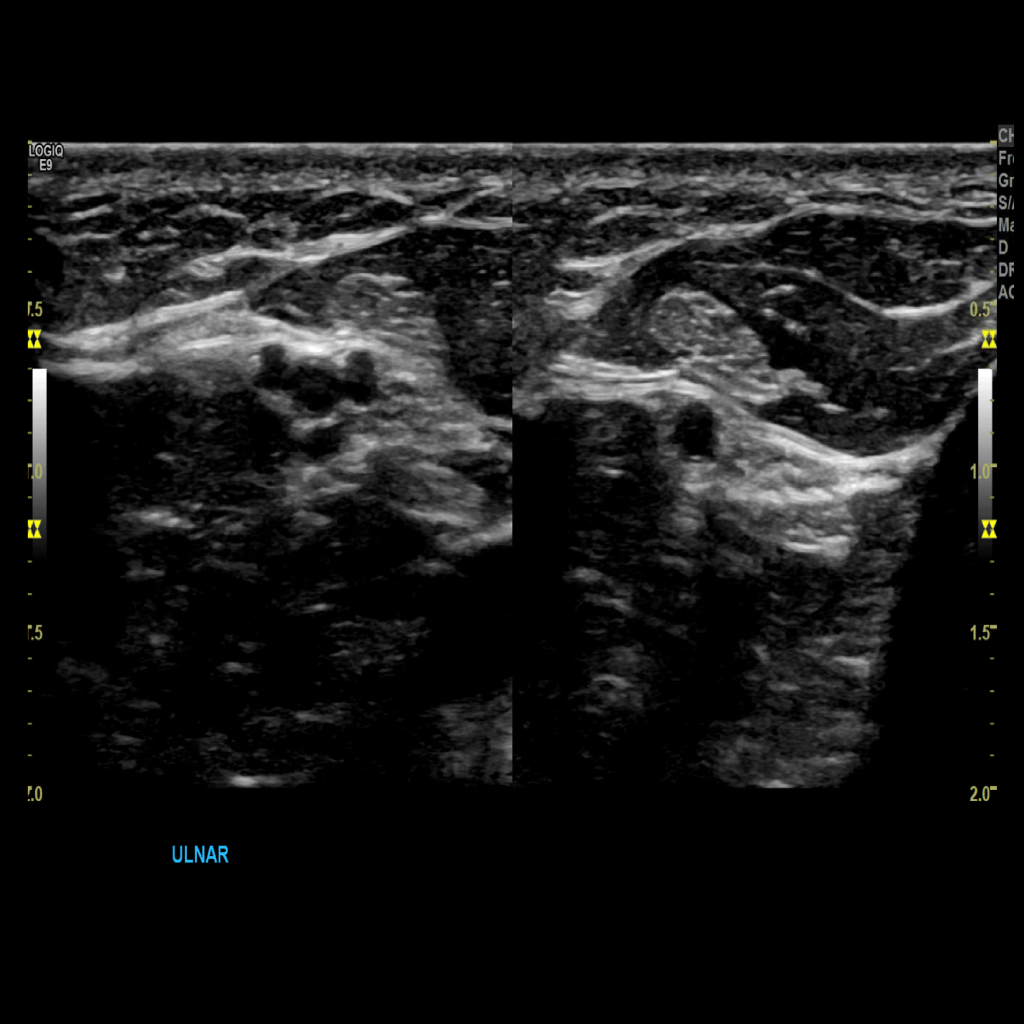

Scan the ulnar veins in grey scale, compression, color doppler and spectral doppler